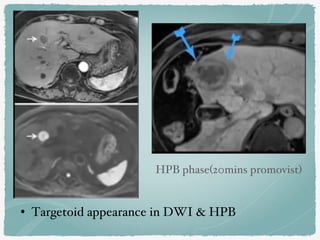

• Targetoid appearance in DWI & HPB

HPB phase(20mins promovist)